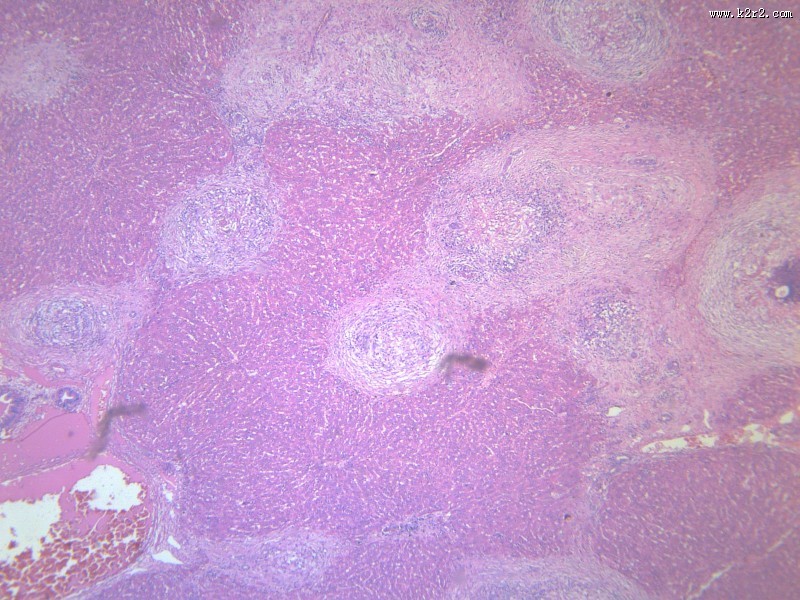

虫卵肉芽肿 - 第4张